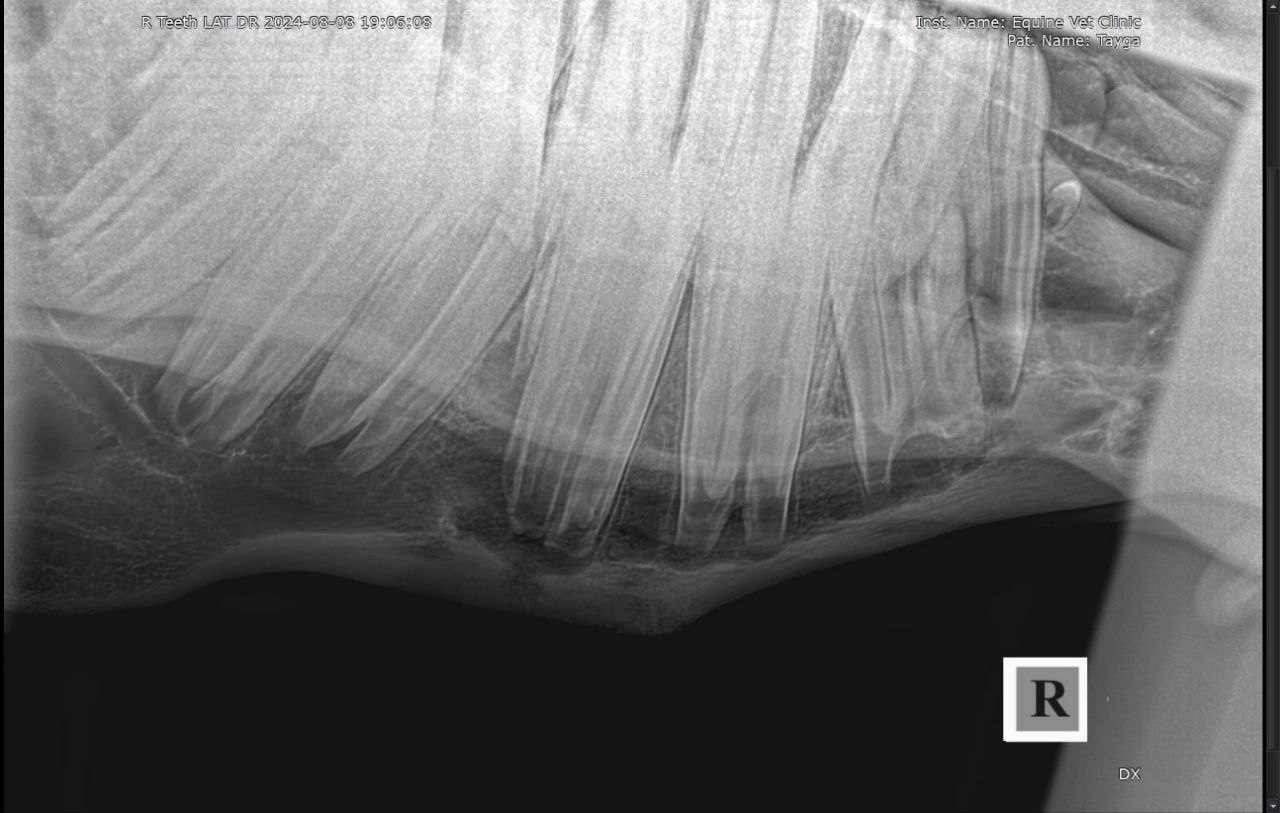

Результаты рентгенологического исследования: наблюдается неравномерная рентгенологическая плотность вокруг верхушки корня и утолщение кортикальной зоны кости нижней челюсти в проекции 408 зуба. Зондированием свища в нижней челюсти установлена вовлеченность корня 408 зуба в формировании канала свища.